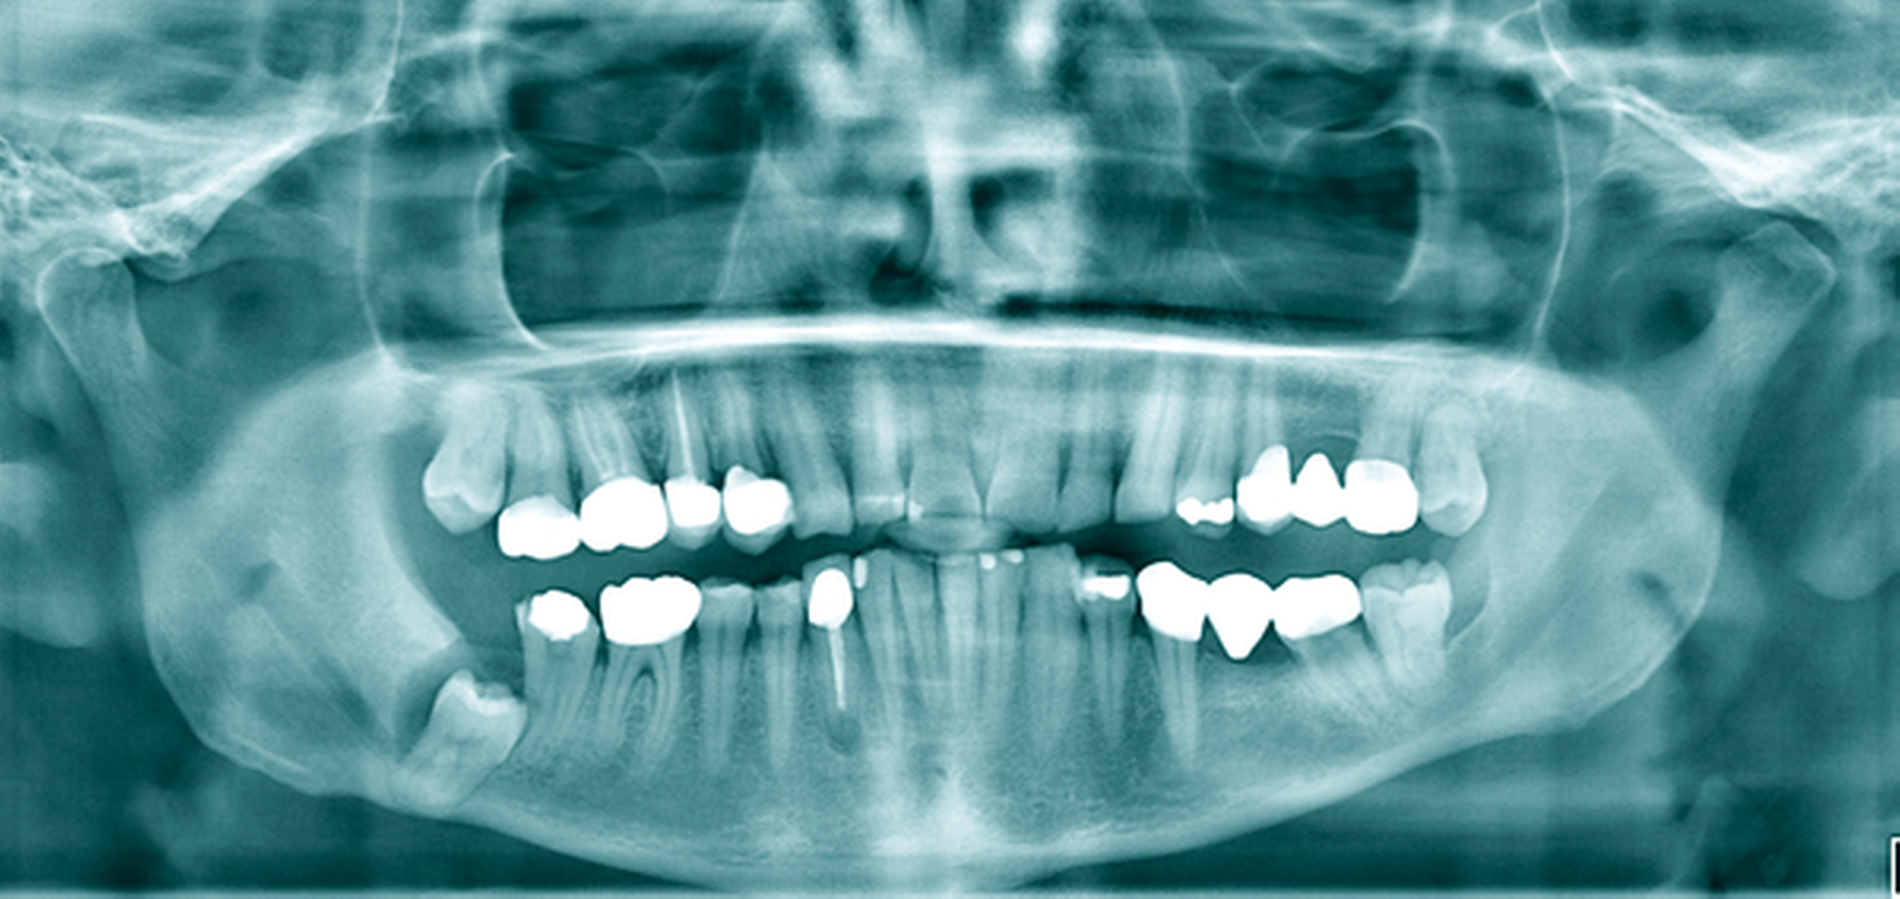

Ein 52-jähriger Patient stellte sich mit Überweisung und Bitte um Therapie einer zystischen Raumforderung im Bereich des rechten Kieferwinkels über unser MVZ vor (Abbildung 6a). Aufgrund der erhöhten Frakturgefahr bei einem weit nach kaudal verlagerten Zahn 48 entschied sich der Patient nach entsprechender Aufklärung für das mehrzeitige Verfahren mittels Zystostomie. Die Versorgung erfolgte in diesem Fall mit einem nicht zahngetragenen Obturator, der lediglich mittels eines Gingivaschildes ins Vestibulum eingelagert war. Der Patient kam damit nach initialer individueller Einpassung gut zurecht. Die radiologischen Kontrollen erfolgten nach histologischer Sicherung einer follikulären Zyste halbjährlich zur Sicherung des Therapieerfolgs. Bei nach elf Monaten deutlich regredientem Befund konnte die Zystektomie und operative Entfernung des Zahnes 48 in ambulanter Allgemeinanästhesie durchgeführt werden, wobei keine perioperativen Komplikationen auftraten (Abbildung 6b). Besonders hervorzuheben ist die Wanderungsbewegung des Zahnes 48 nach koronal. Abbildung 6c zeigt die knöcherne Konsolidierung des Defekts sieben Monate postoperativ bei Beschwerdefreiheit. Bezüglich des vitalen Zahns 47 (ohne Lockerung) wurde eine prothetische Versorgung durch den Hauszahnarzt empfohlen.